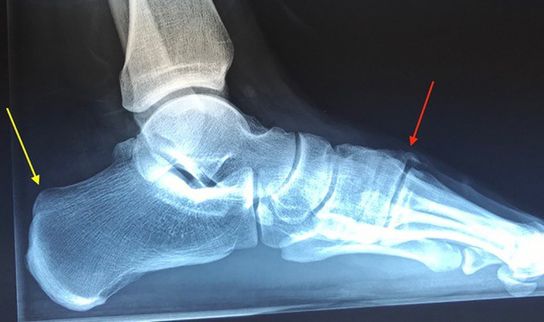

Before: The red arrow shows the arch of the foot. Additionally, the patient had a high heel bone (yellow arrow).

After: The hump of the back of the foot was straightened through the keyhole (percutaneously) and is now no longer disturbing (red arrow). The high heel bone was also removed in the same way (yellow arrow).